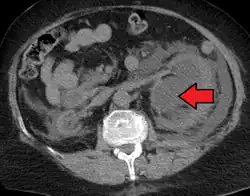

CT scan of bilateral hydronephrosis due to a bladder cancer

- Stone causing hydronephrosis[13]